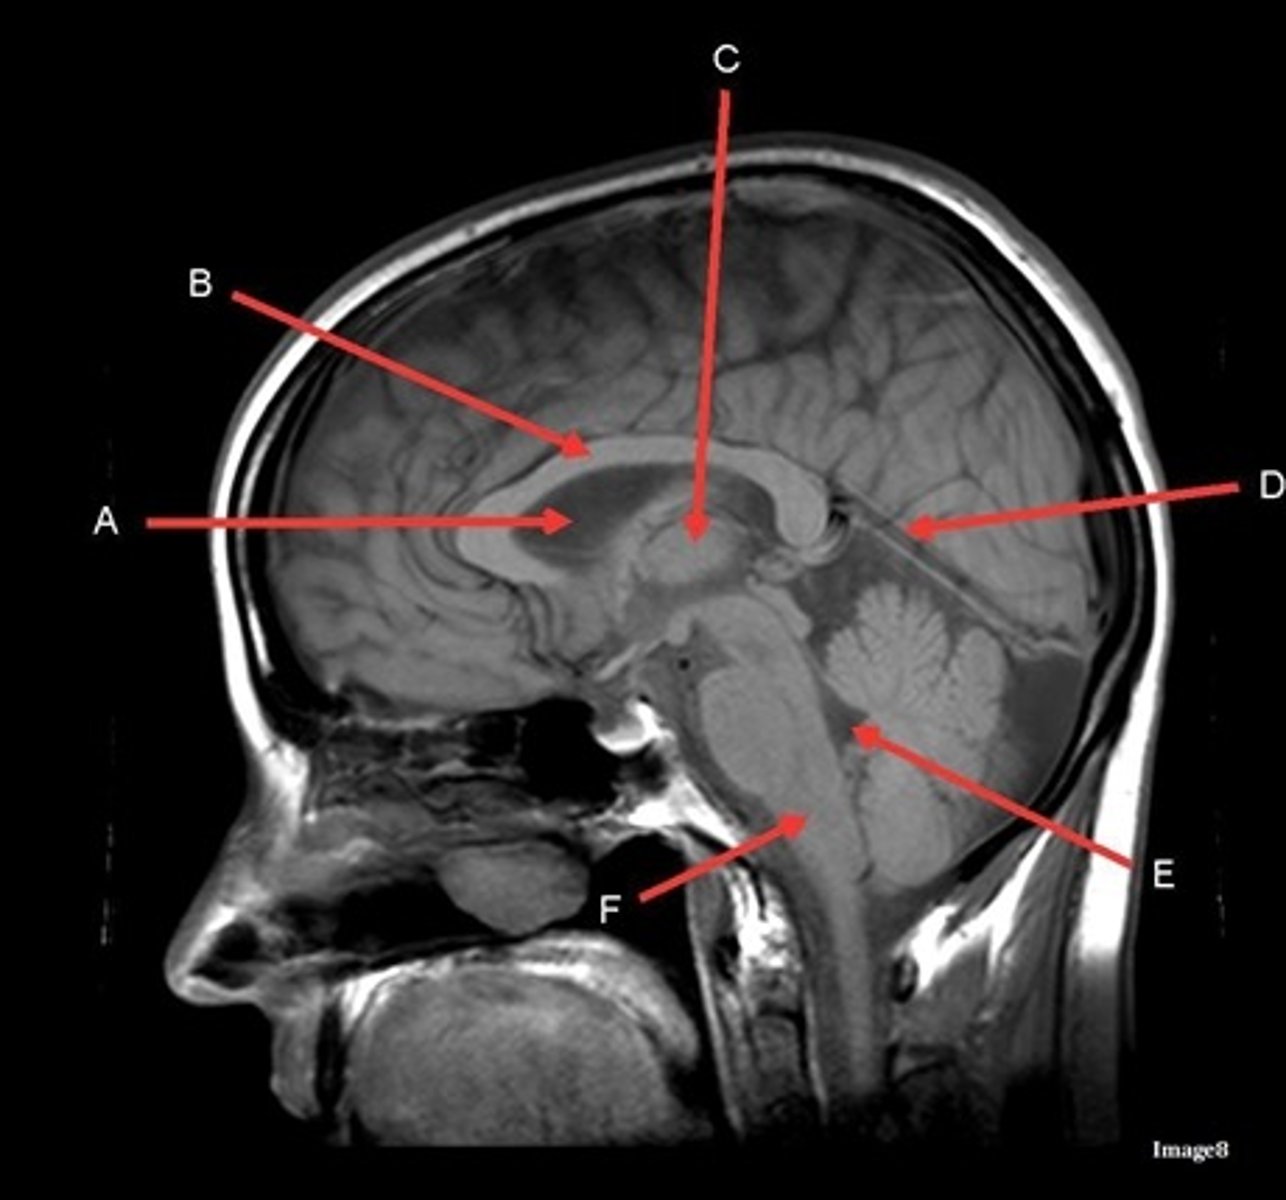

What type of sequence?

T1, sagittal

A- region

Genu of Corpus Callosum

B- region

Splenium of Corpus Callosum

C

pons

D

cerebellum